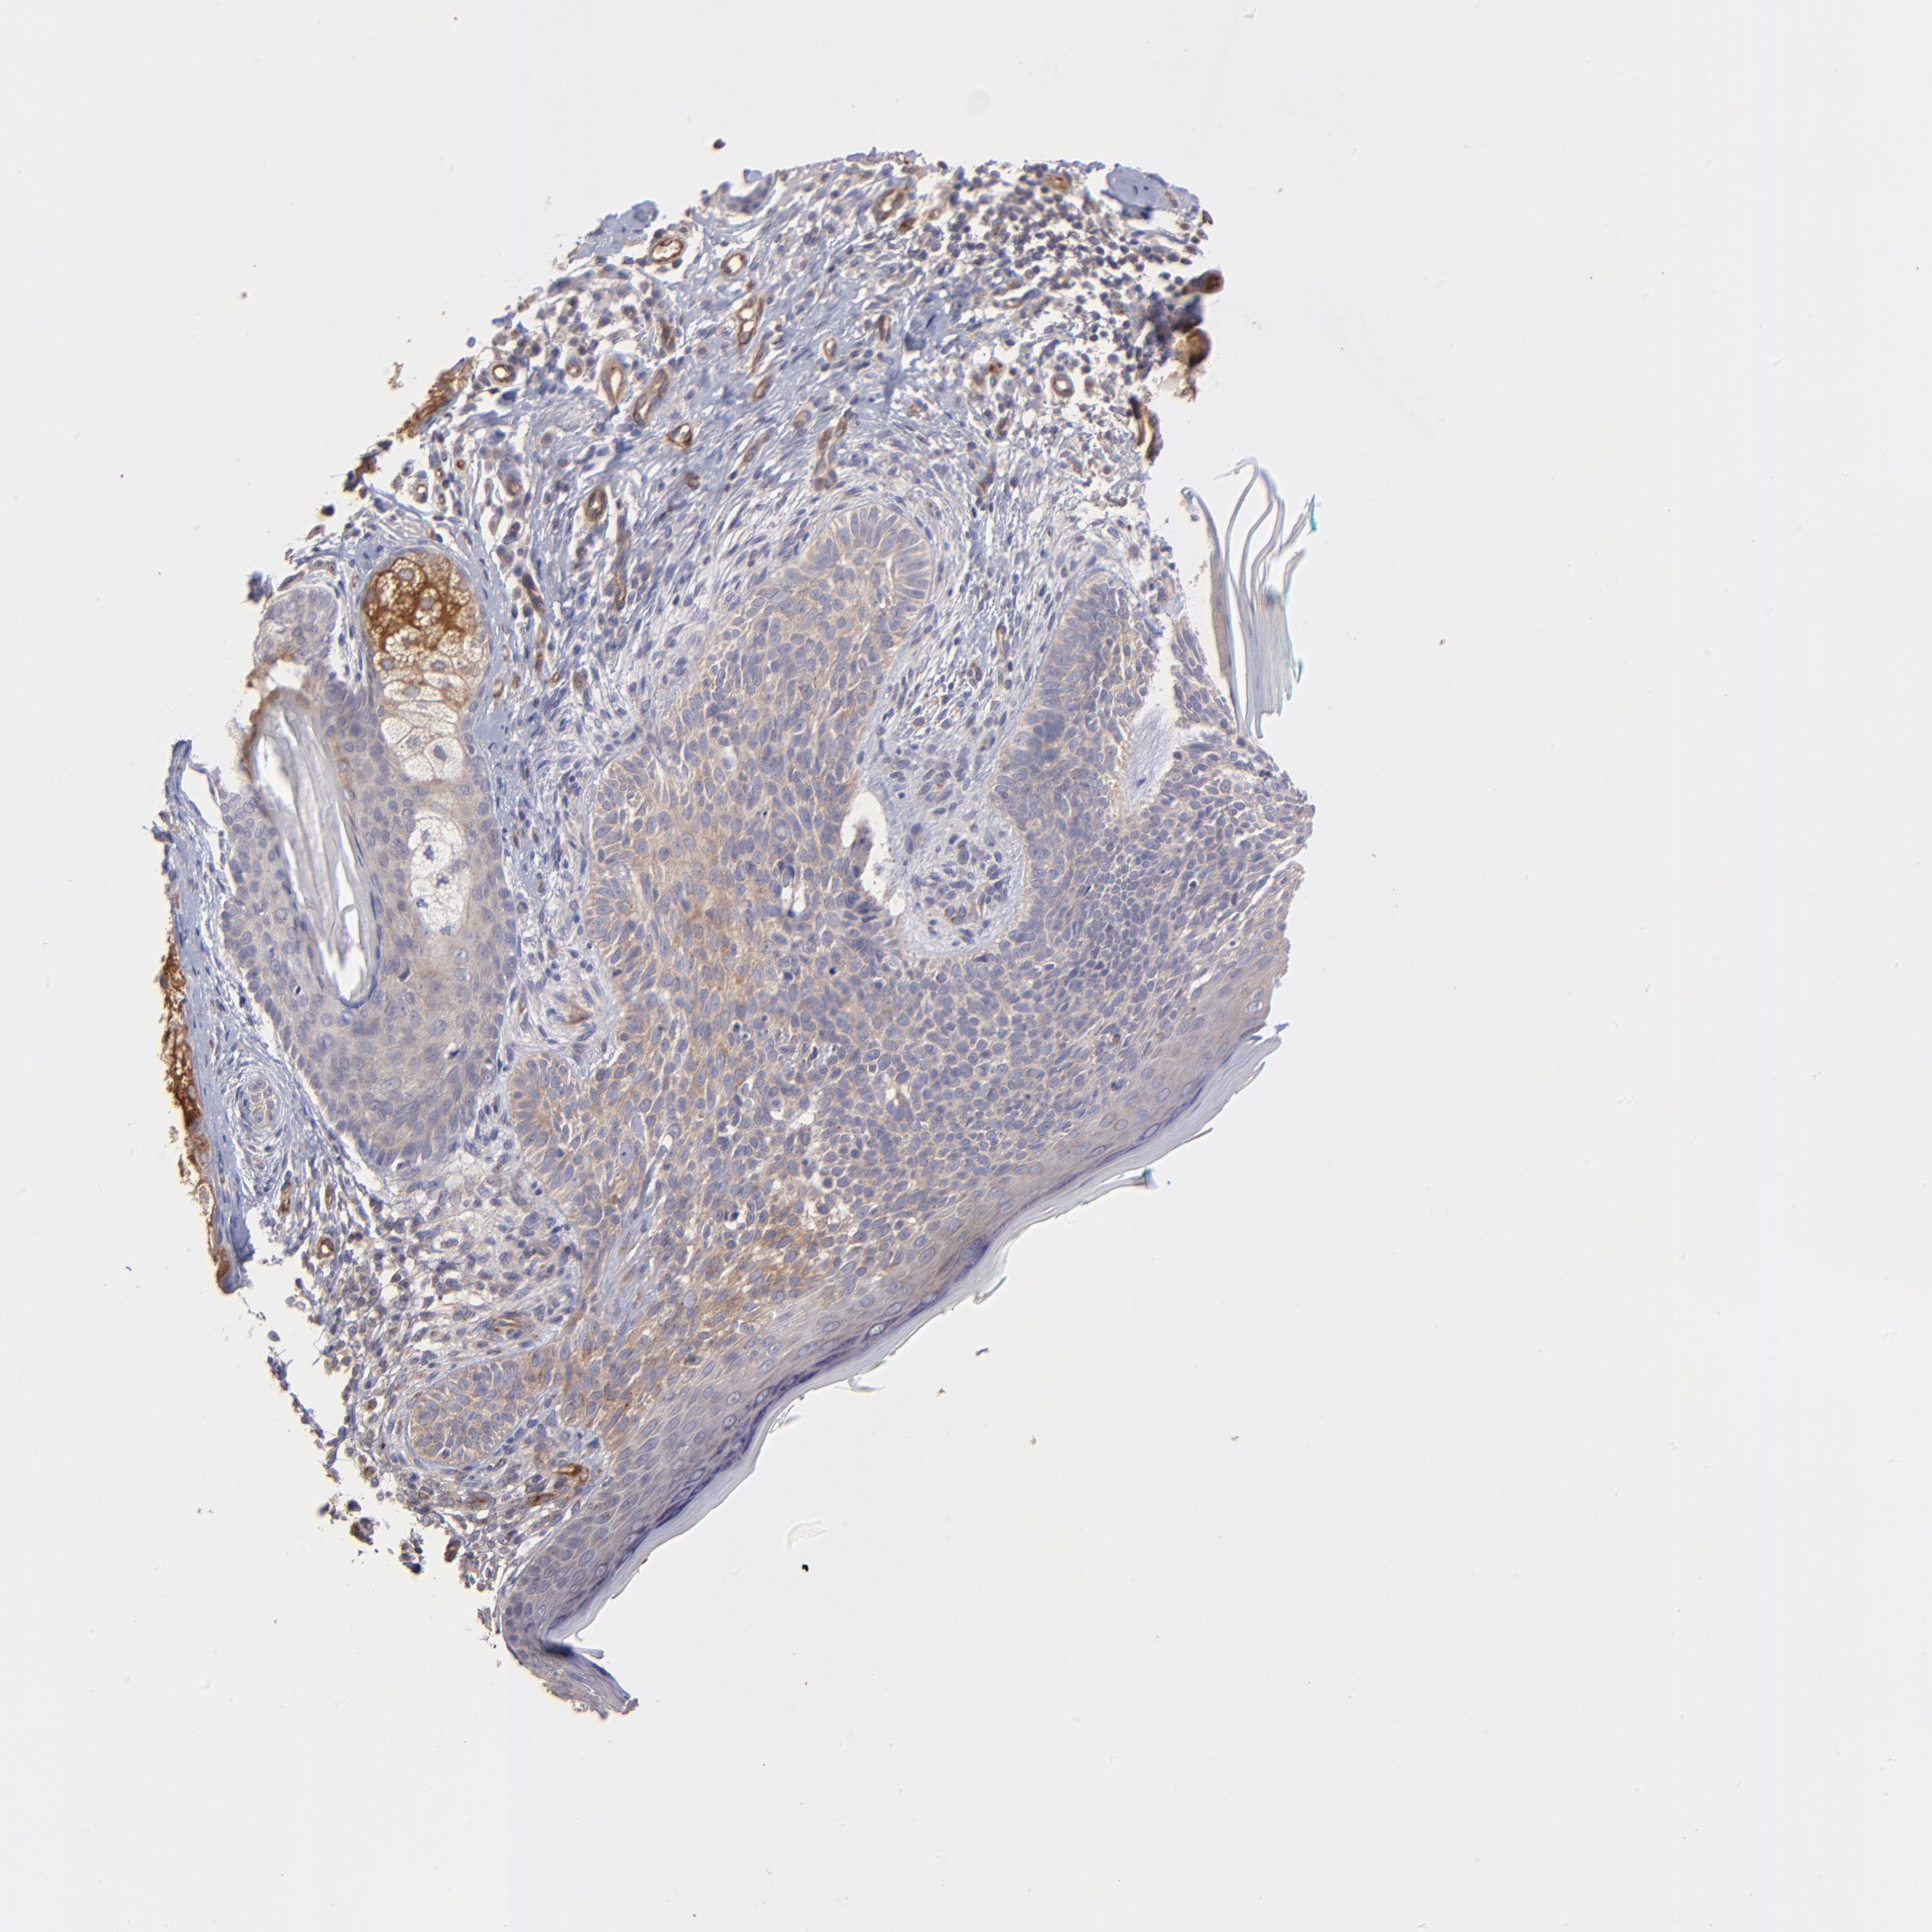

SKIN CANCER - Protein expressioni

A mouse-over function shows sample information and annotation data. Click on an image to view it in a full screen mode. Samples can be filtered based on level of antibody staining by selecting one or several of the following categories: high, medium, low and not detected. The assay and annotation is described here.

Antibody stainingi

Antibody staining in the annotated cell types in the current human tissue is reported as not detected, low, medium, or high, based on conventional immunohistochemistry profiling in selected tissues. This score is based on the combination of the staining intensity and fraction of stained cells.

Each image is clickable and will lead to virtual microscopy that enables deeper exploration of all samples and also displays staining intensity scores, fraction scores and subcellular localization as well as patient and tissue information for each sample.

Antibody HPA003300

Squamous cell carcinoma, NOS

Basal cell carcinoma